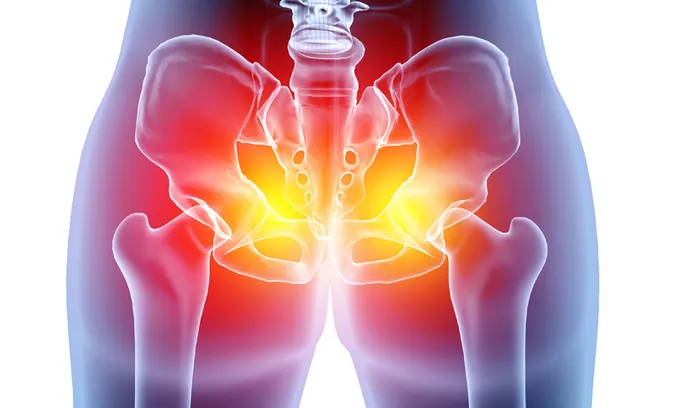

고관절은 골반의 관골구와 대퇴골두를 연결하는 관절입니다. 골반과 다리가 만나는 지점에 위치하며 체중을 지탱하고 다리의 움직임을 가능하게 합니다.

또한 "엉덩이 관절"이라고도 불리는 이 관절은 뼈와 뼈가 연결되어 자유로운 움직임을 가능하게 하는 신체 부위로, 허벅지와 종아리를 포함한 다리 전체를 움직일 수 있도록 돕습니다. 고관절의 움직임과 기능은 걷기, 달리기, 앉기 등과 밀접하게 연관되어 우리 몸의 움직임과 일상 활동에 핵심적인 역할을 수행합니다.

골반 부위에 통증이 나타나면 흔히 "파"로 알려진 "절뚝거림"으로 이어지는 경우가 많습니다. 고관절 통증은 크게 세 가지 방향으로 나뉩니다: ▲서혜부(사타구니) ▲측면 ▲후면으로, 각각의 방향에 따라 의심되는 질환이 달라집니다. 그중 가장 많이 보고되는 증상은 사타구니 통증입니다.

고관절 발달 이형성증이나 대퇴골두 충돌 증후군이 있을 경우, 대퇴골두의 무혈성 괴사가 말초 골절로 확장되면 사타구니 부위에 통증이 발생하는 것이 보통입니다. 고관절 외측의 통증은 주변 연부 조직의 손상 또는 염증으로 인한 대전자 통증 증후군(GTPS)과 관련이 있으며, 고관절 후방 통증은 주변 근육의 긴장이나 비대로 인해 이상근 증후군이 좌골 신경을 압박하는 상황에서 발생할 수 있습니다.